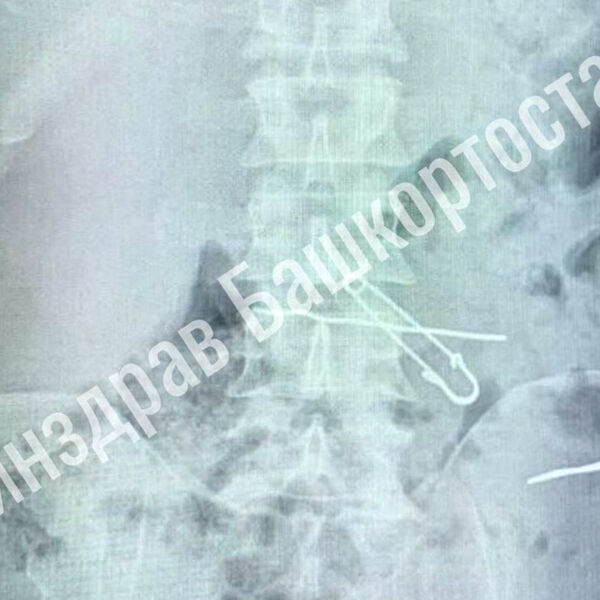

В больницу скорой медицинской помощи поступил мужчина с жалобами на сильные боли в животе. По результатам обследования выяснилось, что у него в толстой кишке находились три металлические скрепки длиной 47, 62 и 90 миллиметров, а в желудке — булавка и проволока.

Пациента срочно госпитализировали в отделение гнойной хирургии, где врачи успешно провели операцию по извлечению всех предметов. Во время вмешательства медики делали контрольные рентгеновские снимки, чтобы убедиться в полном удалении инородных тел. После операции мужчина успешно восстановился и был выписан из медицинского учреждения.